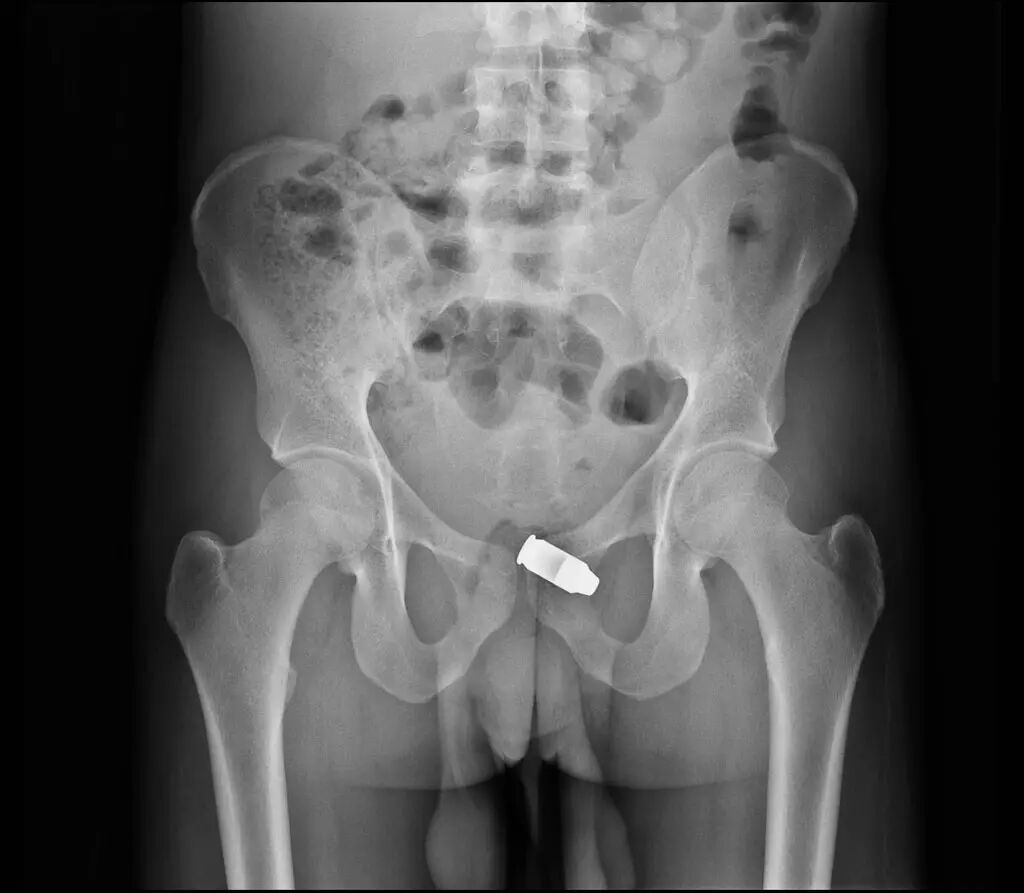

▲肛门内异物:小药瓶